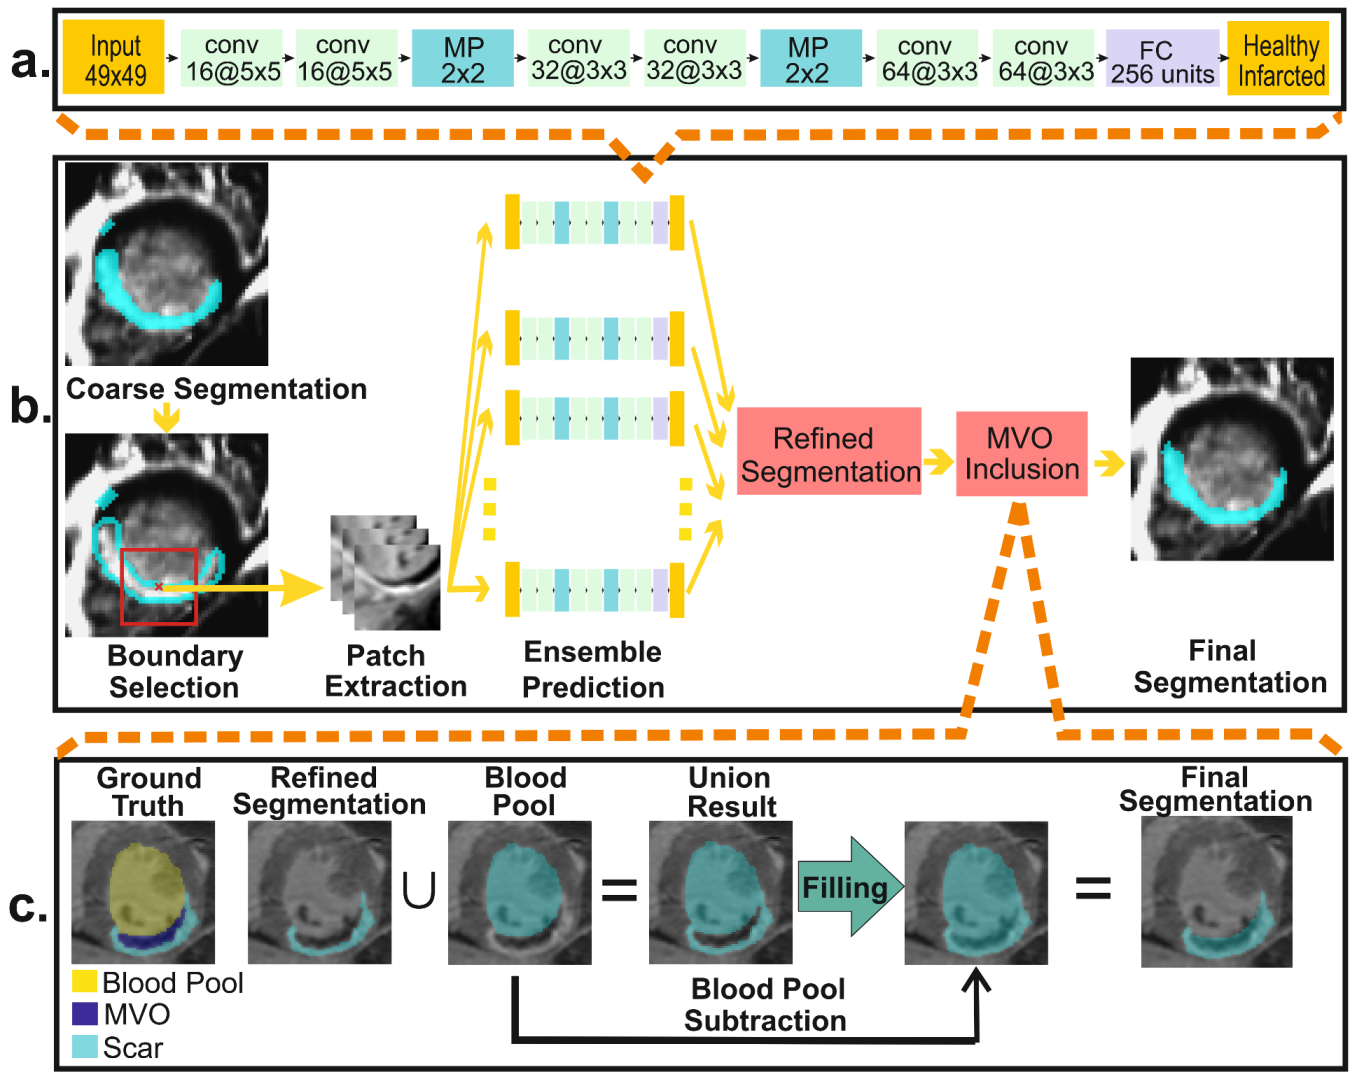

3.2.2. Myocardial Abnormality Detection

3.2.4. Myocardial Scar Quantification: Refined Segmentation

3.2.5. Myocardial Scar Quantification: MVO Inclusion